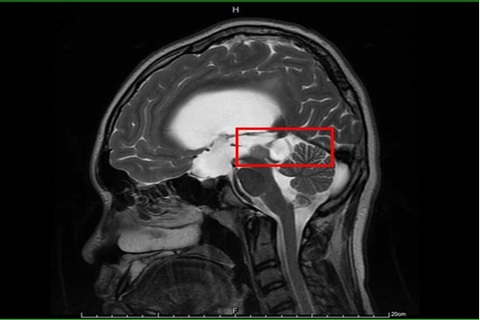

【新唐人亞太台 2020 年 09 月 23 日訊】15歲男孩因頭痛不適昏倒,被家人緊急送醫,經急診診斷疑為水腦合併癲癇,施以抗癲癇藥物治療。但男孩父母對癲癇病情仍有疑慮,故帶至臺大醫院新竹分院小兒神經科門診就醫。透過檢查,發現男孩眼動受限,眼睛無法往上看及往外側注視,醫師問診發現,他自小學四年級就開始頭痛,且因眼動受限而時常跌倒。經腦部核磁共振檢查確診為水腦併中腦腫瘤,立即安排手術治療。

臺大醫院新竹分院小兒部小兒神經科張寶玲醫師表示,在臨床經驗中,頭痛是病童最常抱怨的問題,尤其是小學高年級及國、高中學童;其中大部分為原發性頭痛,如偏頭痛及緊縮型頭痛等。然而,如小朋友有日漸增強或頻率增加之頭痛,且併有不對稱之神經學異常,如:單側肢體無力、抽搐、眼動異常、步態不穩或有全身性症狀,如:發燒或體重下降等,應注意有可能是「繼發性頭痛」,也就是明確病因所引起之頭痛,如:感染或腫瘤所致,提醒民眾應立即就醫治療。